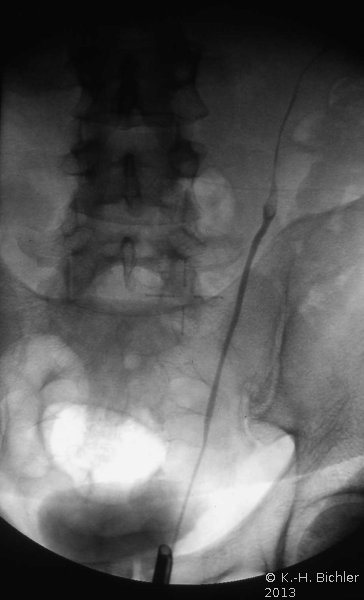

Die Röntgenübersicht der Niere und ableitenden Harnwege zeigten keinen Anhalt für Konkrement. Im Ausscheidungsurogramm eine "stumme Niere" links (Abbildung 19a). Bei der retrograden Sondierung links fand sich keine Abflussbehinderung (Stein oder Stenose) (Abbildung 19c). Im MCU kein Anhalt für Reflux (Abbildung 19b). Im Nierenfunktionsszintigramm MAG3 wurde eine seitengetrennte Funktionsverteilung von rechts zu links wie 93% zu 7% festgestellt. Zur Abklärung eventueller Gefäßalterationen erfolgte eine Renovasographie mit dem Nachweis einer langstreckigen Stenose der linken Arteria renalis (Abbildung 19d). Wegen des Verdachtes auf eine generalisierte Arteriitis wurden Angiographien weiterer Gefäßgebiete durchgeführt: Dabei fanden sich eine geringgradige Einengung der infrarenalen Aorta und der linken Arteria subclavia.

Diagnose: Generalisierte Arteriitis - Takayasu-Syndrom

Die Behandlung umfasste neben der perkutanen, transluminalen Dilatation der A. renalis die systemische Behandlung mit Cortison und β-Blocker. Unter dieser Behandlung kam es zur Verbesserung der linksseitigen Nierenfunktion auf 30%. Das AUR zeigte eine zeitgerechte Kontrastmittelausscheidung (Abbildung 20). Im weiteren Verlauf ist evtl. eine neuerliche Dilatation erforderlich bzw. eine operative Versorgung der Nierenarterienstenose.